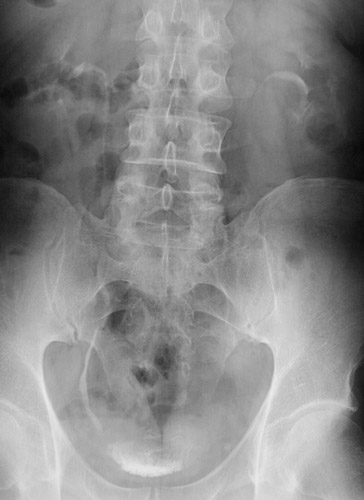

This intravenous pyelogram demonstrates a ureteral calculus at the vesicoureteral junction on the left where there is a filling defect. A closer view is seen below.